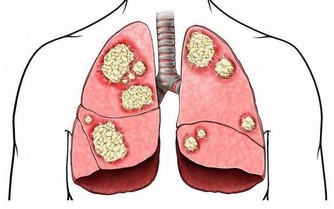

甲減是甲狀腺分泌的甲狀腺激素過少而引發的一種疾病。當甲減發生時,人體新陳代謝減慢,血脂的利用率就會變低,並且在血液中積累、升高,從而引起了高血脂。

而當血脂積累過多就會沉積在血管壁上,並逐步形成動脈粥樣硬化斑塊,造成血管變得狹窄,從而導致心腦血管疾病風險蹭蹭漲~